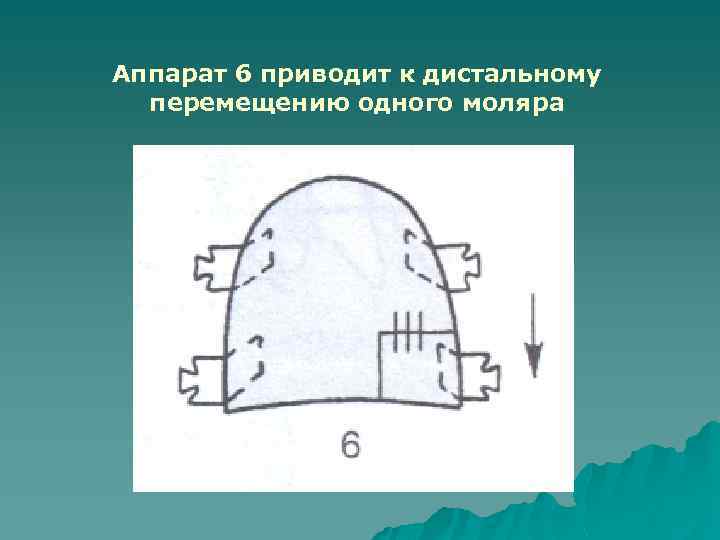

Аппарат 6 приводит к дистальному перемещению одного моляра